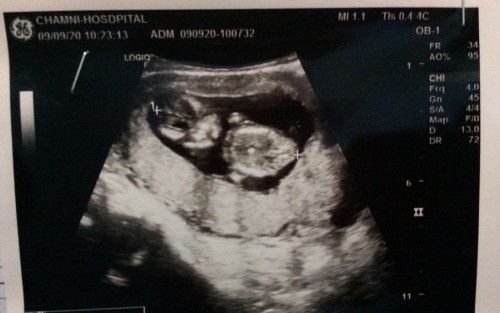

13W.คะ ดูไม่เป็นคะในใบซาวเป็นส่วนไหนของเด็กคะ ท้องแรกคะ😛

ทั้งตัวคะ ซ้ายมือคือหัวขวาลำตัว